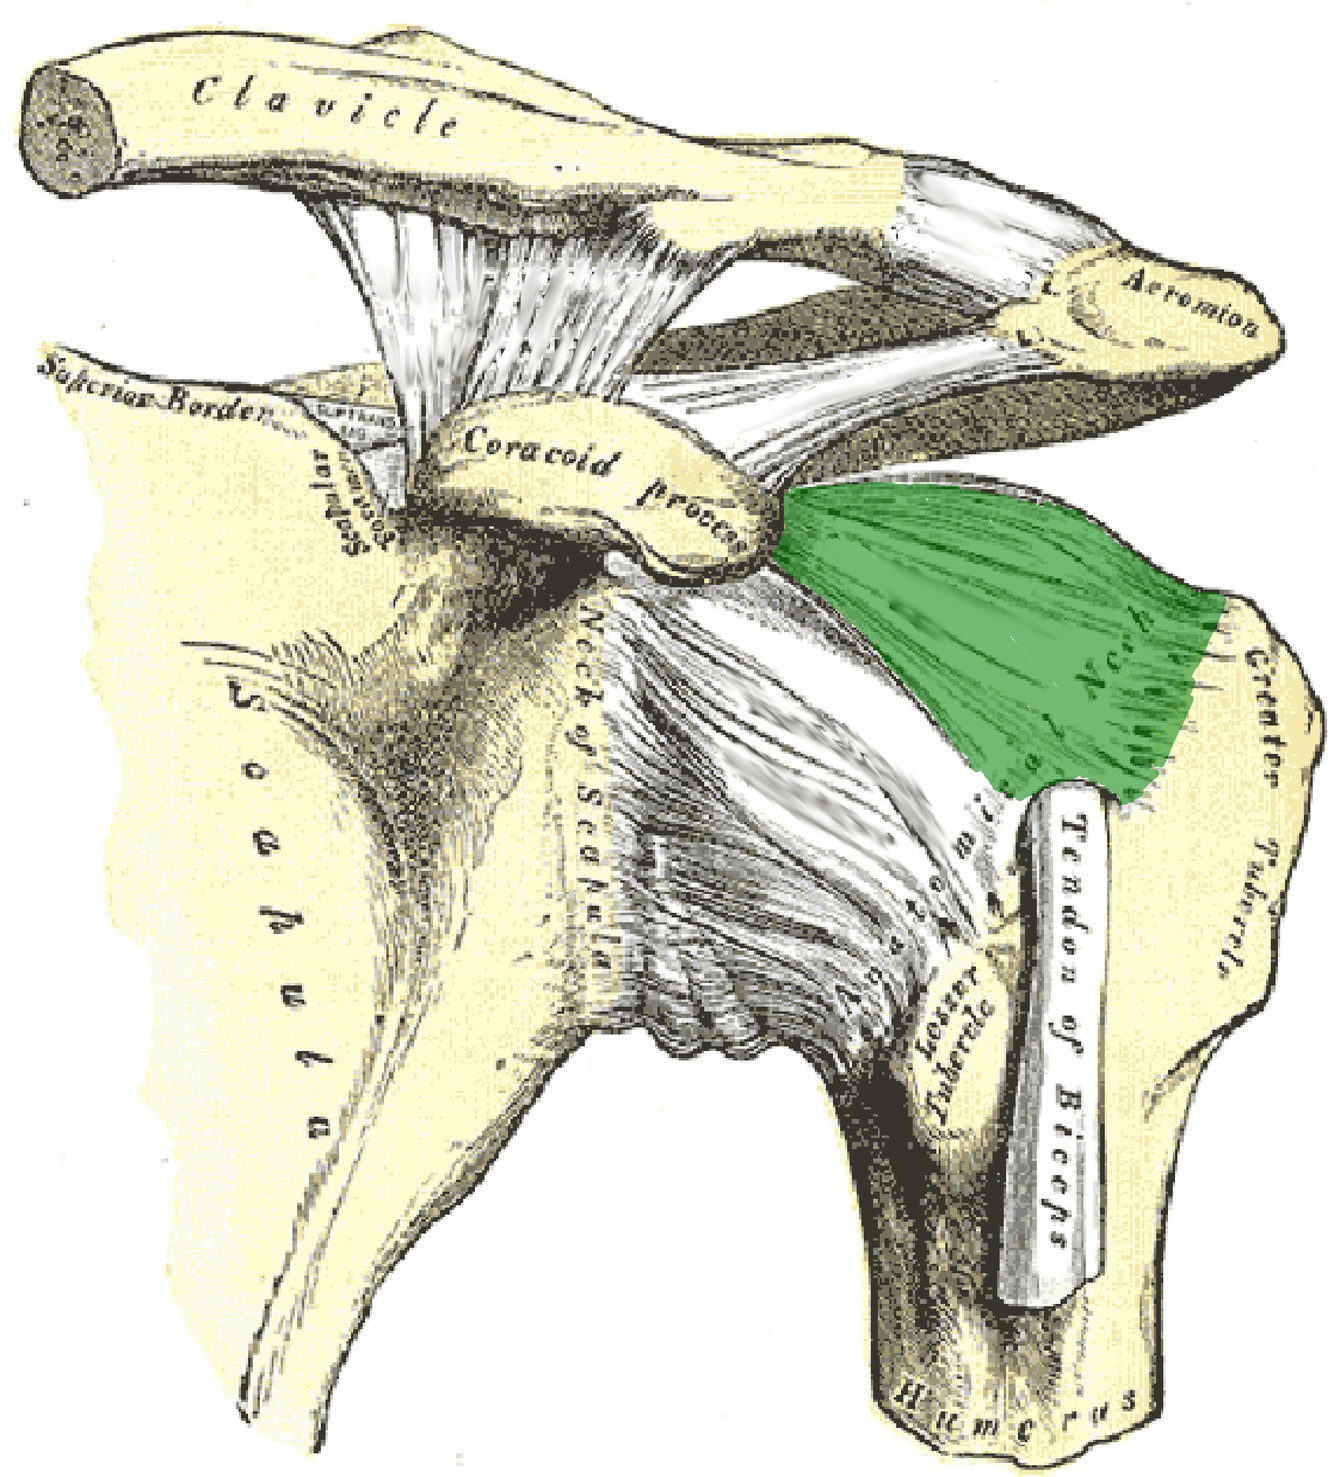

What is this structure?

Coracohumeral ligament of the shoulder